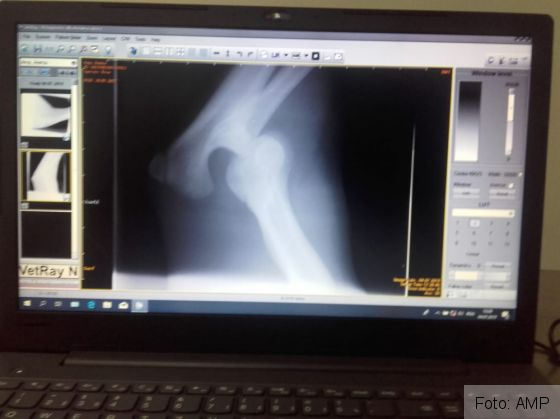

„Astăzi i-a fost făcută o radiografie care a confirmat temerile medicilor veterinari colaboratori ai AMP: fractură de femur cu deplasare la piciorul drept, spate. Radiografia a scos însă la iveală și o problemă mai veche, la piciorul drept-față al ursoaicei: o luxație de articulație, cu posibilă ruptură de ligamente. Rezultatele vor ajunge astăzi în Germania, la medicul veterinar specialist care sperăm să o opereze pe tânăra ursoaică. Acum așteptăm cu toții costurile estimative ale intervenției, dar și o dată aproximativă în care poate fi efectuată operația”, a precizat Paula Ciotloș, reprezentantă AMP. Persoanele care vor să-i ajute pe cei de la AMP s-o salveze pe Anima pot găsi detalii AICI!